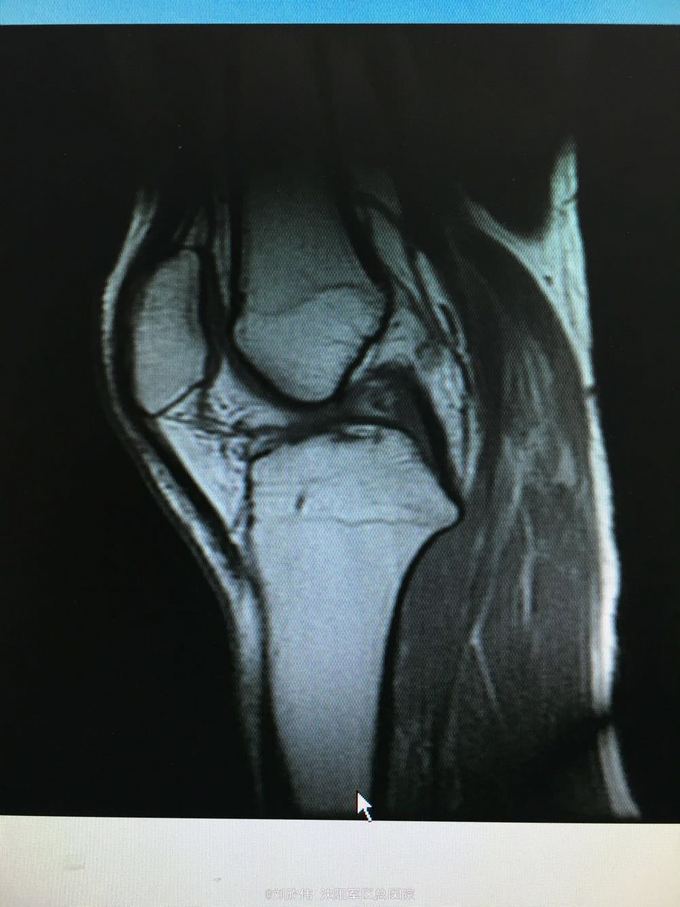

训练致右膝肿痛伴活动受限3个月 自觉脱臼感

右膝lachman试验,轴移试验阳性 MRI提示ACL已显示不清,半月板后角高信号(但术中未见撕裂,mri存在假阳性)

右膝前交叉韧带断裂 右膝半月板损伤 手术方法如题,直接上图